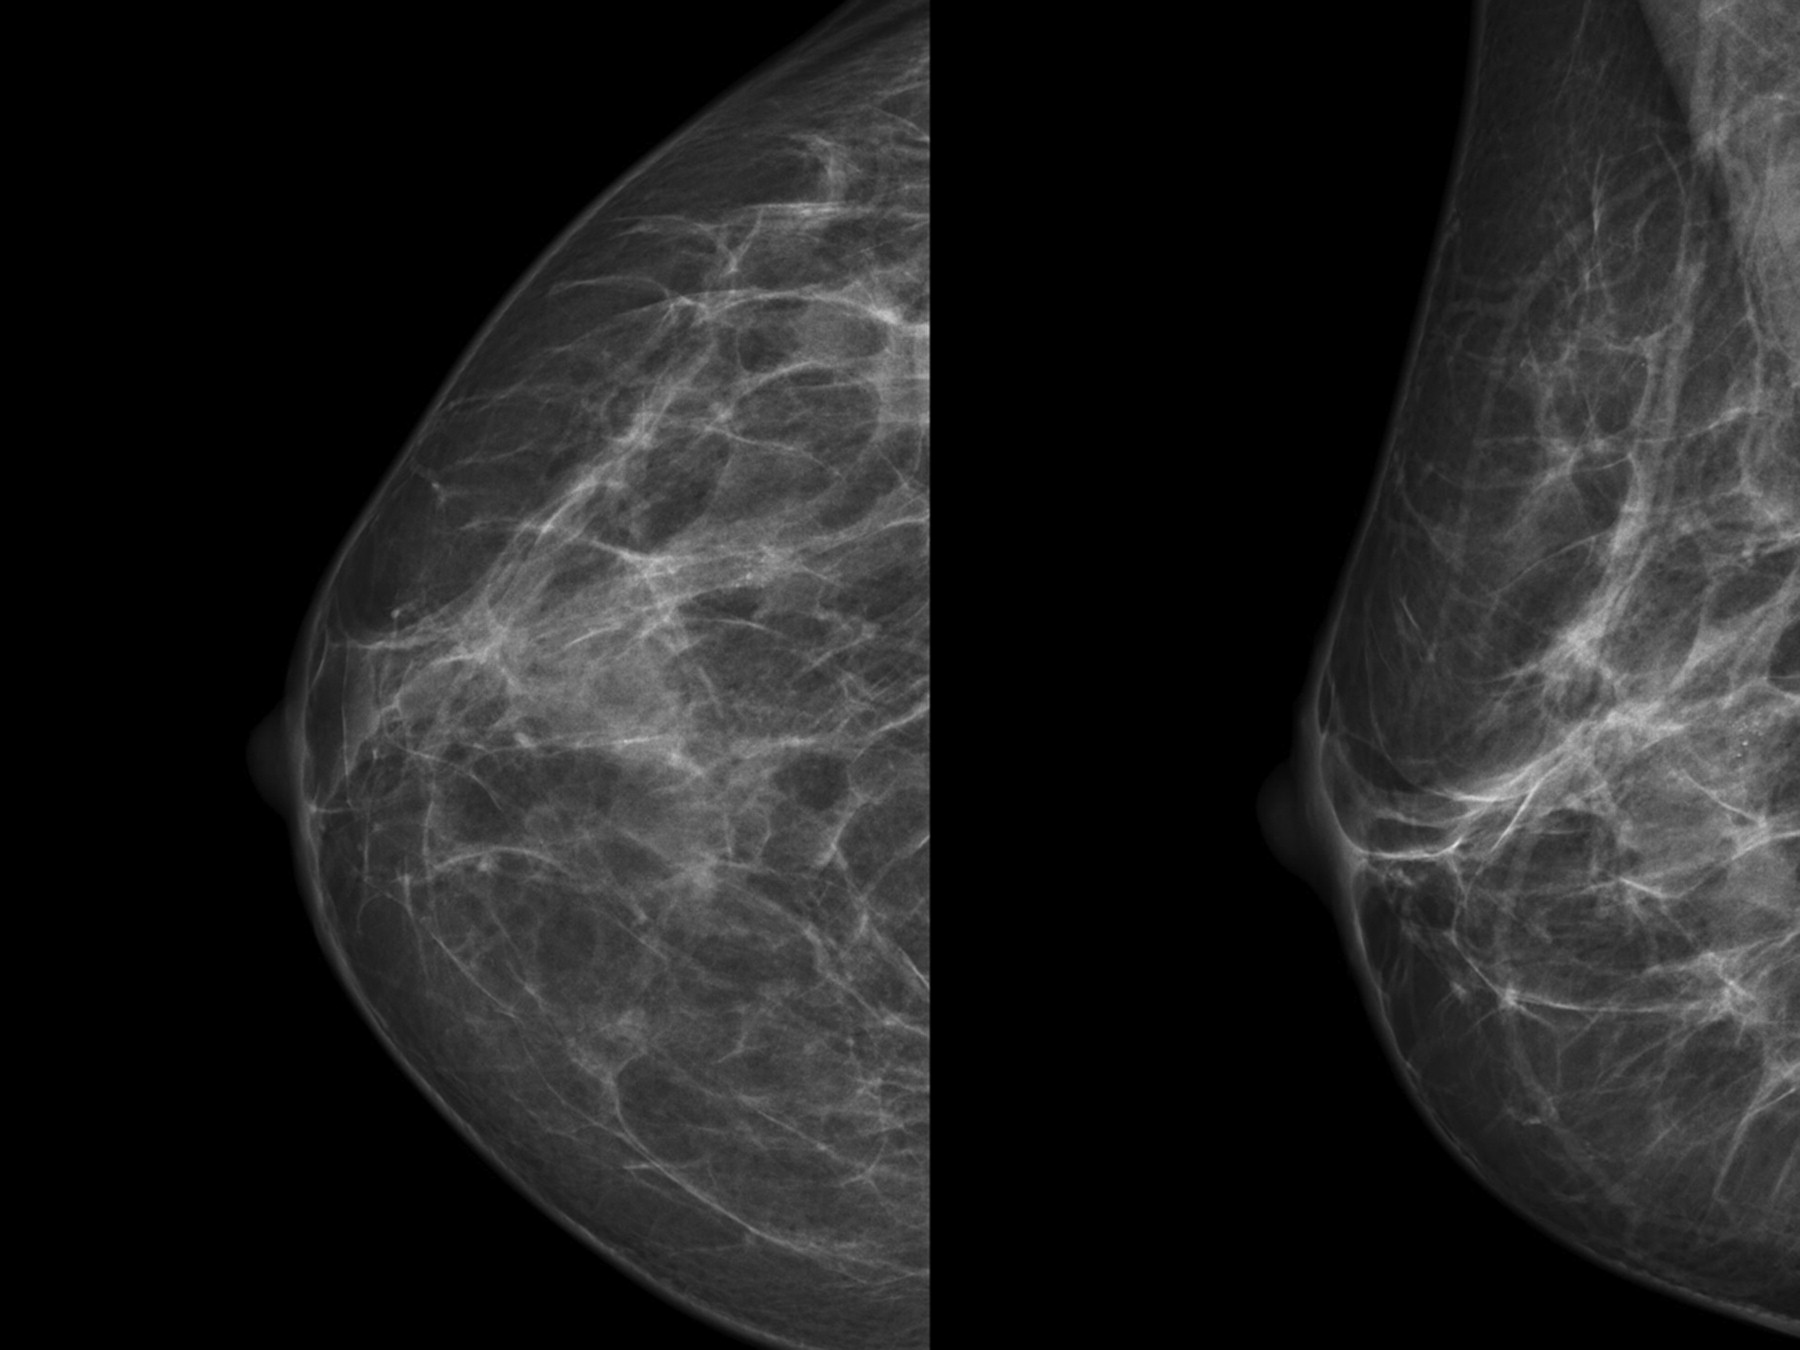

They appear as white spots or flecks on a mammogram but can't be felt during a breast exam. A new group has formed. For women treated for breast cancer in the past, calcifications may also be due.

There are numerous causes for calcium deposits in the breasts, including: But, japanese food natto has the ability to decalcify and maintain uniform level of calcium throughout the body and parts. Breast calcifications. california pacific medical center:

There are a significant number. This is especially good for. Calcifications in a noncancerous growth called a fibroadenoma.